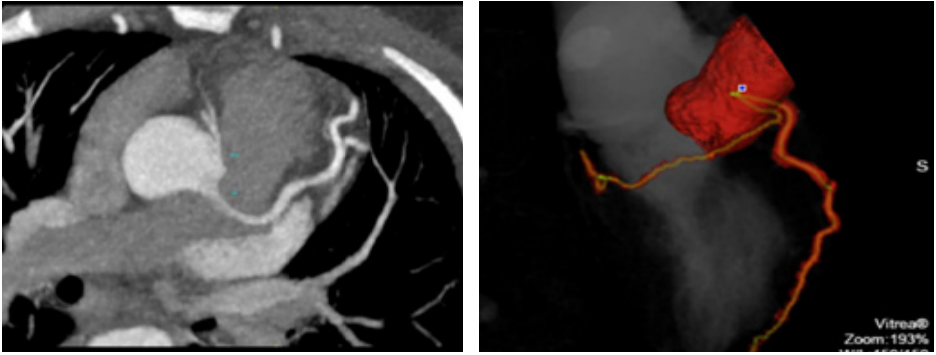

A 32 years young woman with history of hypertension, dyslipidaemia and active smoking, presented to the Emergency Department of our hospital with symptoms of unstable angina pectoris. The patient was a diagnosed case of Mid-Aortic-Syndrome with bilateral renal artery stenosis (2000) and underwent resection of the stenotic intermesenterial aortic segment with implantation of PTFE-Prosthesis and bilateral implantation of renal arteries at the very young age of 12 years. Her physical examination was unremarkable with no evidence of dyspnoea, lung congestion, murmurs or signs of raised jugular venous pulse (JVP). Her heart rate was 76 bpm and the blood pressure was stable at 130/80 mm Hg. Her daily medication was Aspirin 100 mg, Candesartan 32mg, Bisoprolol 7.5mg and Atorvastatin 40mg. An electrocardiogram (Figure 1) on admission demonstrated sinus rhythm with early repolarisation changes and laboratory analysis revealed normal blood count with normal liver and kidney functions. Initially, the cardiac biomarker (Troponin T) was 34pg/ml (normal range < 14 pg/ml) but follow up results showed a significant rise from 34pg/mL to 661 pg/mL. With the diagnosis of an acute myocardial infarction on the basis of a sudden exponential change in the Troponin levels, the patient underwent coronary angiography through the right femoral artery route (Figure 2), which revealed a disease free left main coronary artery. We were unable to identify the RCA ostium, for which an Aortography was performed and it revealed the RCA originating from left coronary sinus. Further confirmation of the anomality was done through a coronary computed tomography angiography (Figure 3). The coronary computed tomography angiography (CCTA) showed the anomalous origin of a hypoplastic RCA from left coronary sinus ventral to the left main origin, lying between the aorta and the pulmonary trunk with a negative Agatston score. The transthoracic echocardiogram revealed a normal left ventricular function without any regional wall motion abnormalities, diastolic dysfunction Grade II and minimal mitral- and tricuspid-regurgitation. Laboratory investigation for cardiotropic virus marker revealed increased values of IgG-EBV, which most probably reflects an old Epstein-Barr virus (EBV) Infection.

Figure 3 Coronary CT Angiography.